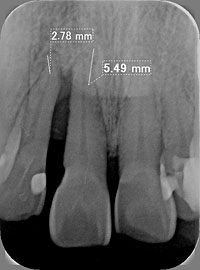

歯牙の動揺が著しく、骨を回復させた後に歯を冠(ブリッジ:かぶせもの)にて連結固定して保存が可能となった症例

術前 エムドゲイン適応 術後

(レントゲン上で骨が2〜5o回復)